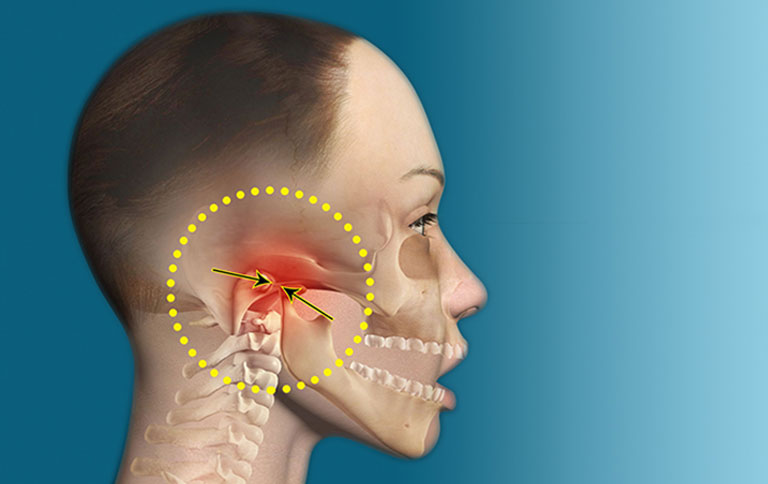

Triệu chứng và dấu hiệu nhận biết loạn năng khớp thái dương hàm

Hậu quả của loạn năng khớp thái dương hàm nếu không chữa trị

Bệnh nhân bị suy nhược, thiếu hụt chất dinh dưỡng do hoạt động ăn nhai phải chịu nhiều áp lực như đau nhức hay mỏi cơ hàm. Dần dần hình thành cảm giác biếng ăn.

Cơn đau xuất hiện thường xuyên hơn, thậm chí ngay cả khi há miệng ra, có thể không há được miệng.

Nếu không được điều trị kịp thời thì rối loạn khớp thái dương hàm có thể làm ảnh hưởng đến các phần xương khớp có liên quan và xuất hiện viêm nhiễm khó điều trị.

Gây ra khả năng bị lệch mặt và sai khớp cắn ảnh hưởng đến thẩm mỹ khuôn mặt.